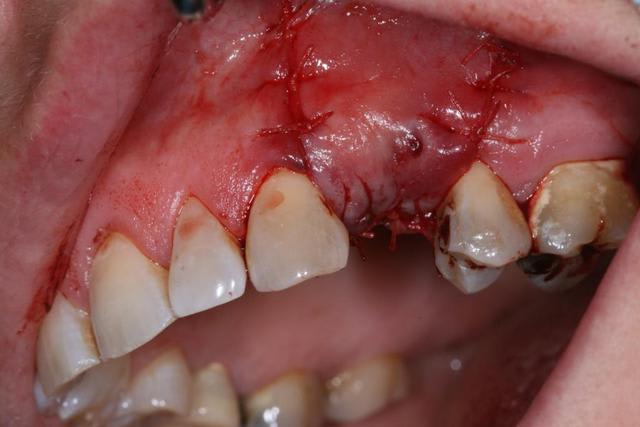

suite

exposition membrane; ça arrive, mais c'est pas grave.

pose implants

cicatrisation gingivale